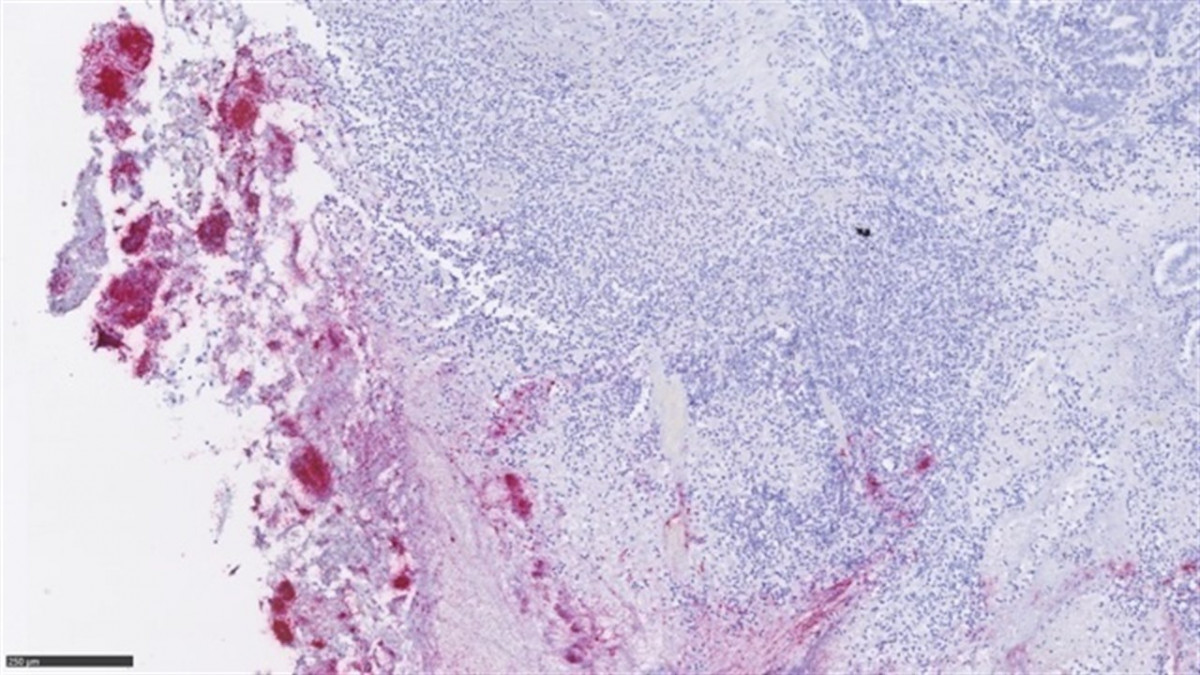

Microbiota metstasis

Liderado por el Dana-Farber Cancer Institute, el estudio ha aclarado que las fusobacterias, un tipo de bacterias de la microbiota que suelen estar en la cavidad oral, pueden crecer en otros sitios en condiciones de enfermedad, como tumores, después de encontrarlas en cáncer colorrectal.

Así, han descubierto que estas bacterias se encuentran dentro de la célula, tanto en el tumor como en la metástasis.

El trabajo, en el que han participado también otros profesionales del Campus Vall d'Hebron, junto a cinco centros estadounidenses, ha comparado la microbiota en el tumor primario del cáncer y en la metástasis hepática del mismo paciente, y han detectado que ambas microbiotas son "básicamente las mismas".